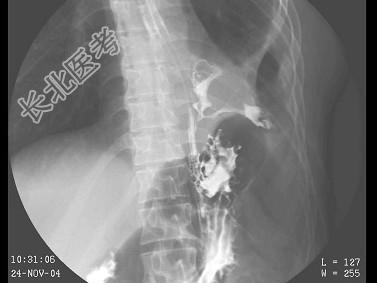

- 单项选择题女,39岁, 左下肺叶切除术后。体检:左下肺呼吸音弱, 行胸腔闭式引流术,引流出脓性分泌物。结合图像, 最可能的诊断为 ( )

E、食管下段胸腔瘘